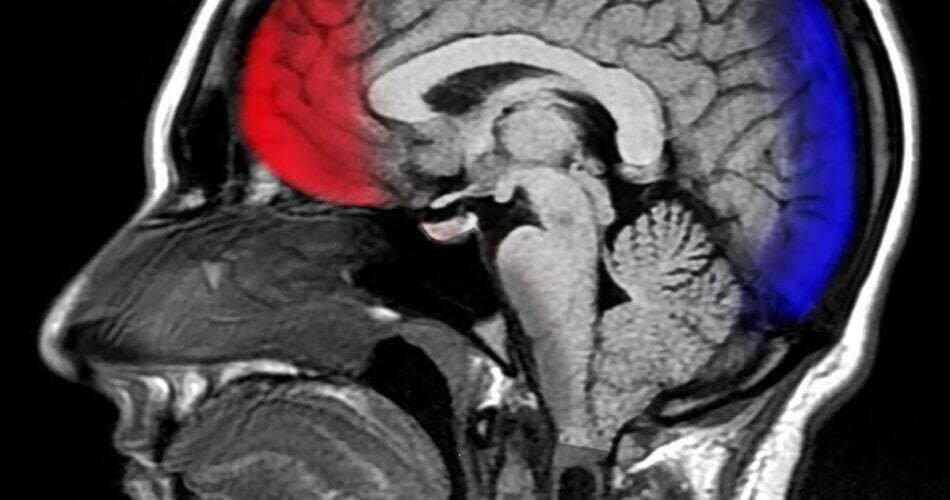

Lorsqu’on leur a demandé s’ils voulaient donner les fonds à une œuvre de bienfaisance afin de montrer leur gratitude, ceux qui ont décidé de faire un don avaient un modèle d’activité cérébrale différent de ceux qui ne le faisaient pas. Cependant, la meilleure partie était: «Les participants qui avaient terminé la tâche de gratitude des mois plus tôt ont non seulement déclaré se sentir plus reconnaissants deux semaines après la tâche que les membres du groupe témoin, mais aussi, des mois plus tard, ont montré plus d’activité cérébrale liée à la gratitude. dans le scanner.

Les chercheurs ont décrit ces effets neuronaux «profonds» et «durables» comme «particulièrement remarquables», a expliqué Christian Jarret en psychologie.